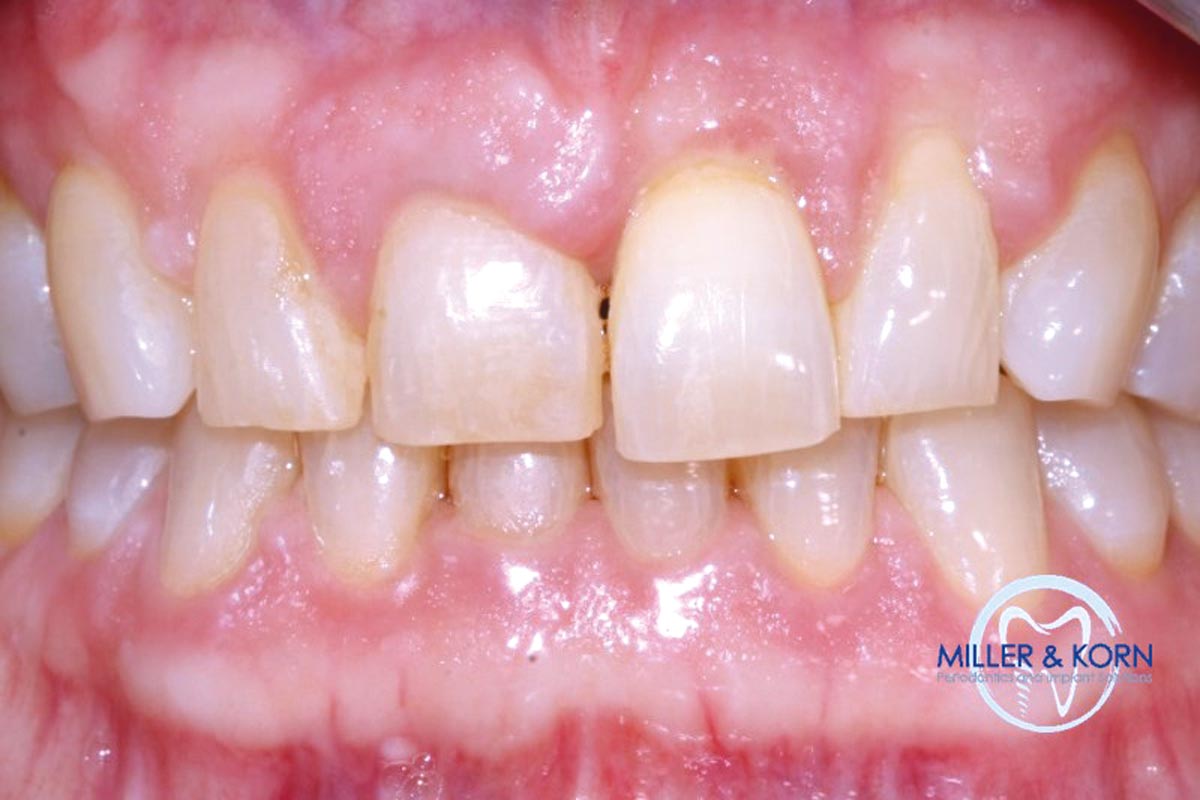

32/39 - Preoperative clinical situationImmediate implant placement and correction of horizontal and vertical bone loss using an allograft bone ring, cerabone® and Jason® membrane - Drs. Miller and Korn

33/39 - Preoperative clinical situationImmediate implant placement and correction of horizontal and vertical bone loss using an allograft bone ring, cerabone® and Jason® membrane - Drs. Miller and Korn